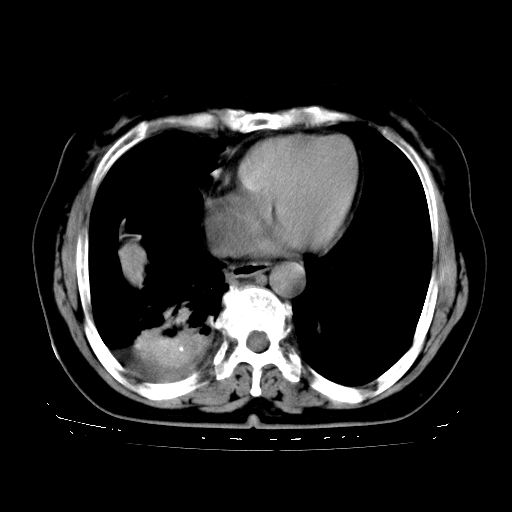

以下是引用zhangzhongshou在2008-3-22 12:52:00的发言:[br]1、右侧液气胸。[br]2、腹水。建议进一步检查。

以下是引用鲁巨ct在2008-3-22 14:10:00的发言:[br]1、右侧液气胸,右中下叶节段性不张。[br]2、腹水,建议上腹部ct检查

以下是引用zjzjr在2008-3-22 17:19:00的发言:[br]1、右侧液气胸,右下叶节段性不张。[br]2、腹水,建议上腹部ct检查